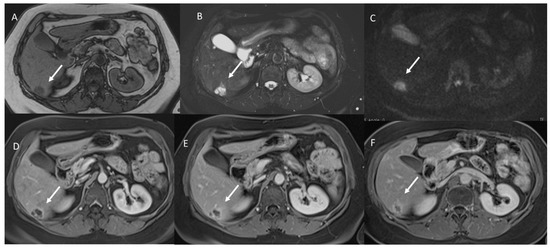

- The signal intensity (SI) in T1 W, in T2-W, DWI sequences and the apparent diffusion coefficient (ADC) map.

3.2. T2-W Signal Intensity and Diffusion

3.3. Arterial Phase Appearance

3.4. Portal Phase Appearance

3.5. Equilibrium Phase Appearance